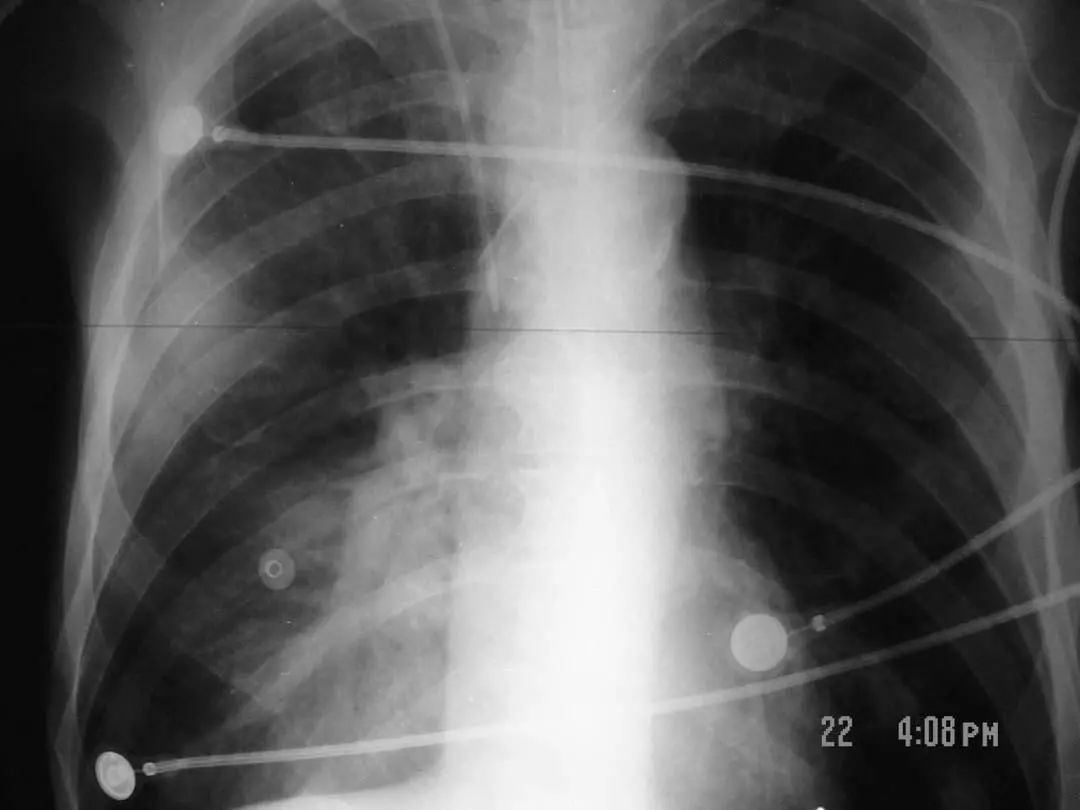

图1.4 53岁的严重军团菌肺炎患者。胸片显示双肺下叶致密实变。

图1.10 48岁的流感嗜血杆菌性肺炎患者, 胸部X线片显示双侧不透明,主要分布在外周。